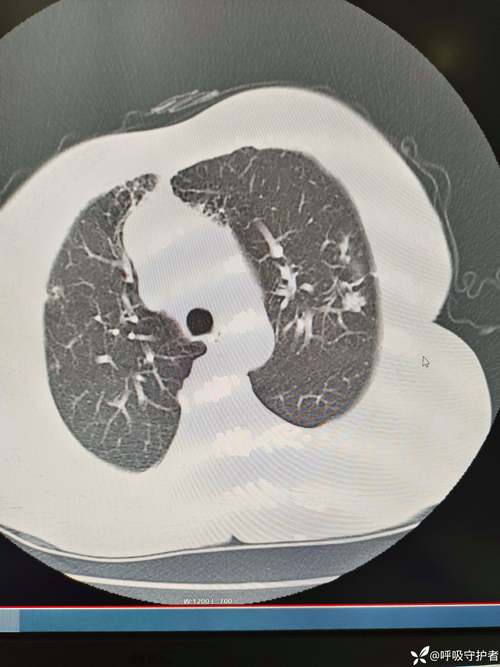

- 影像学检查:

- 胸部X光片:是诊断肺炎最直接、最重要的方法,可以显示肺部有无炎症浸润、肺不张等病变。